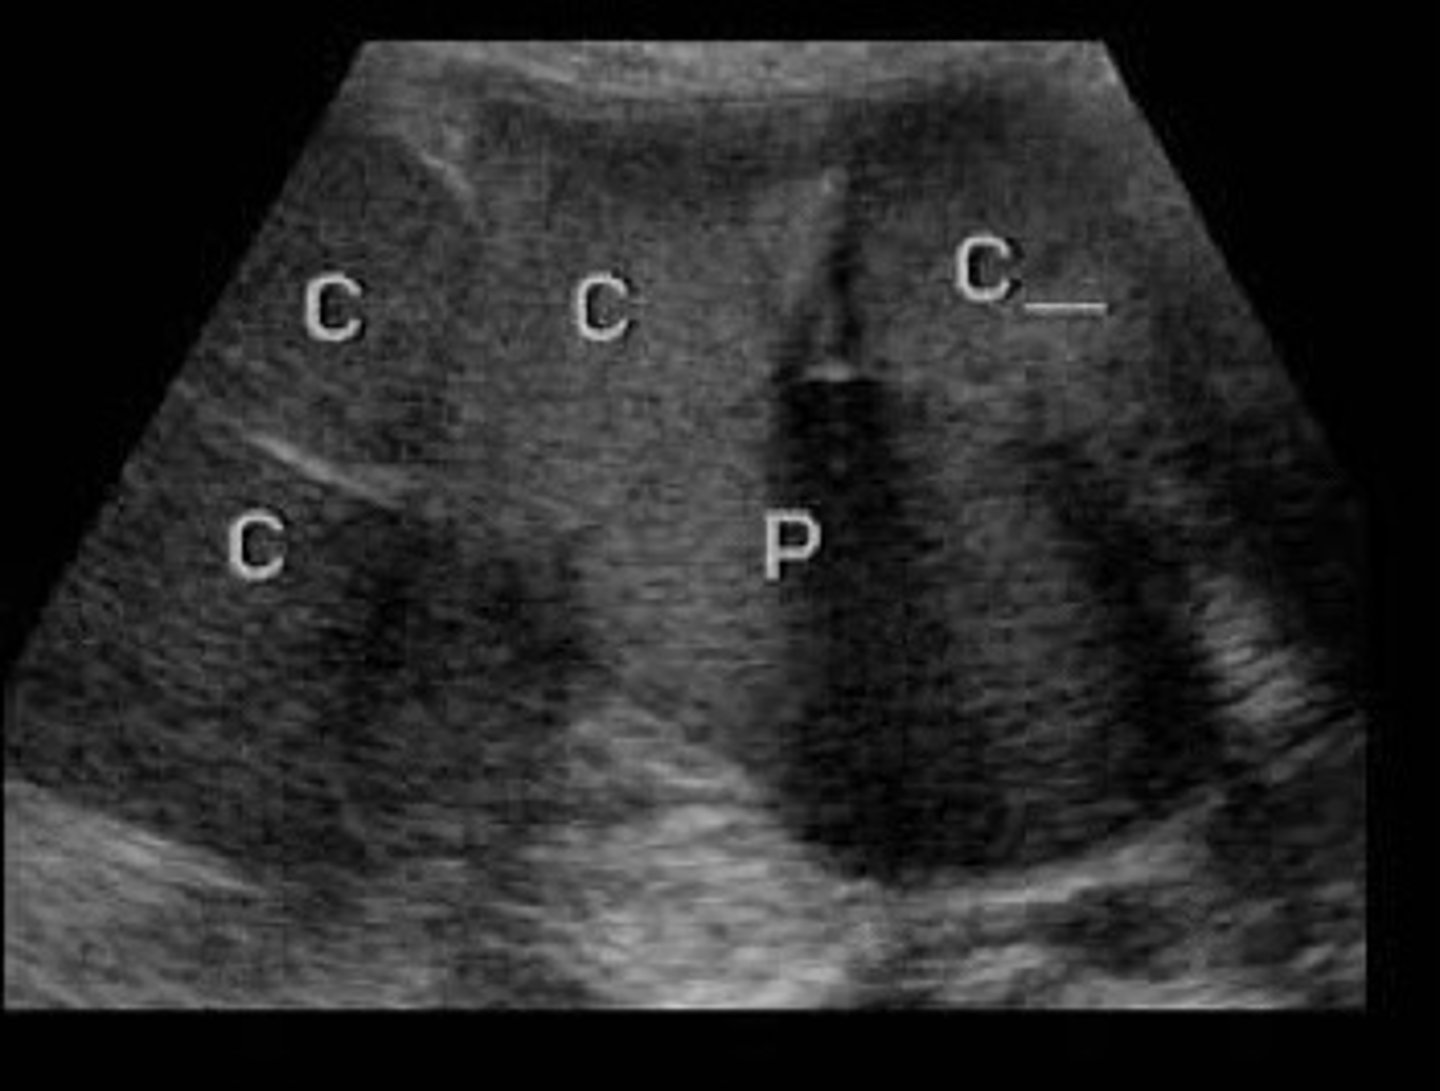

Nephrolithiasis

What does this image show

Echogenic focus or foci with posterior shadowing

Describe the sonographic appearance of nephrolithiasis